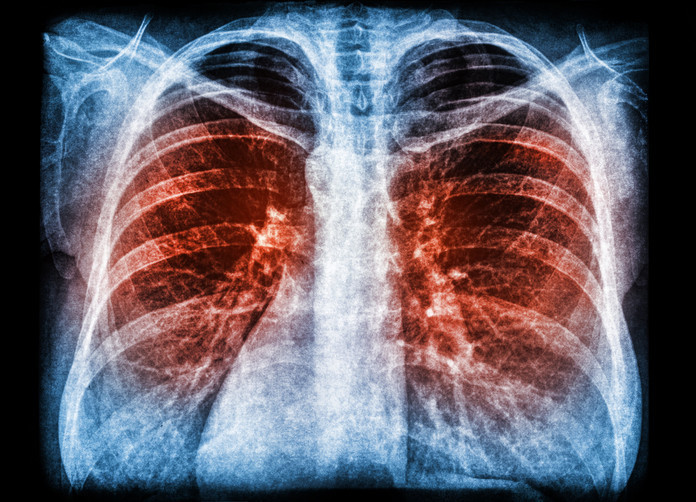

Dünya genelinde yaklaşık 1,8 milyar insan sigara içiyor. Her gün yaklaşık 22 bin kişi sigaraya bağlı nedenlerle hayatını kaybediyor. Sigara, akciğer kanserlerinin yüzde 80’inin başlıca nedenidir.

Bununla birlikte bağırsak, mesane, prostat kanserleri ve lenfomalar da dahil olmak üzere neredeyse tüm kanser türlerinde etkisini görmek mümkündür.